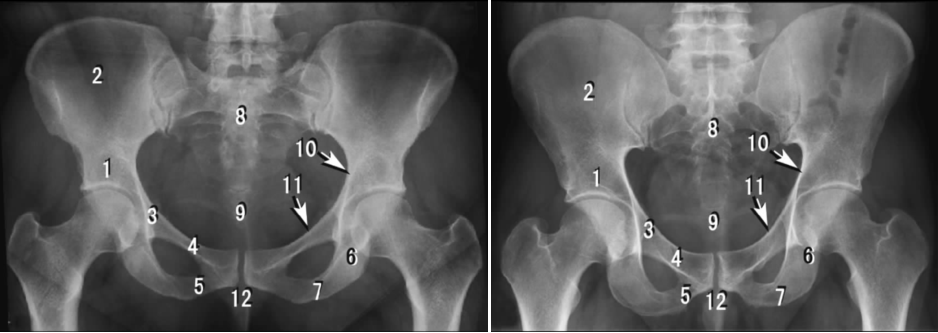

4 四肢X线作业